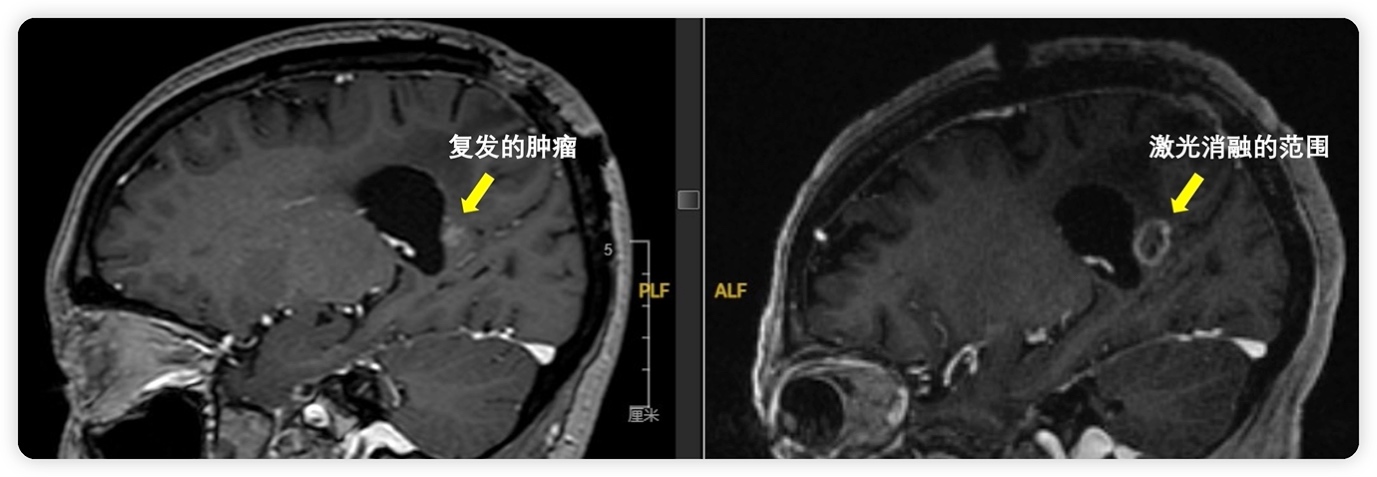

图3:患者术前术后影像资料对比

术后,宋女士恢复良好,复查影像证实,复发肿瘤已被完全消融。杨学军主任表示:“对于位于大脑深部、功能区或多次复发的脑肿瘤,激光间质热疗提供了一种更优的微创选择。我们希望通过推广此类技术,让更多面临困境的患者看到新的希望。”